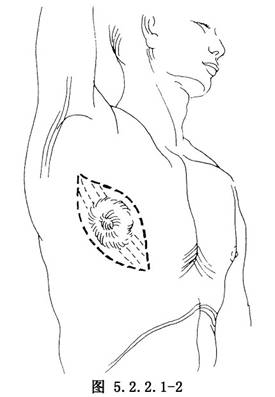

(1)切口:根據腫瘤的範圍,在腫瘤未侵及淺層肌肉和皮膚時,可沿瘤體的長徑作切口(圖5.2.2.1-1)。若腫瘤已累及皮膚,應沿瘤體的長徑作梭形切口,切緣距腫瘤3cm以外,連同受累的皮膚、肌層與腫瘤一併切除(圖5.2.2.1-2)。